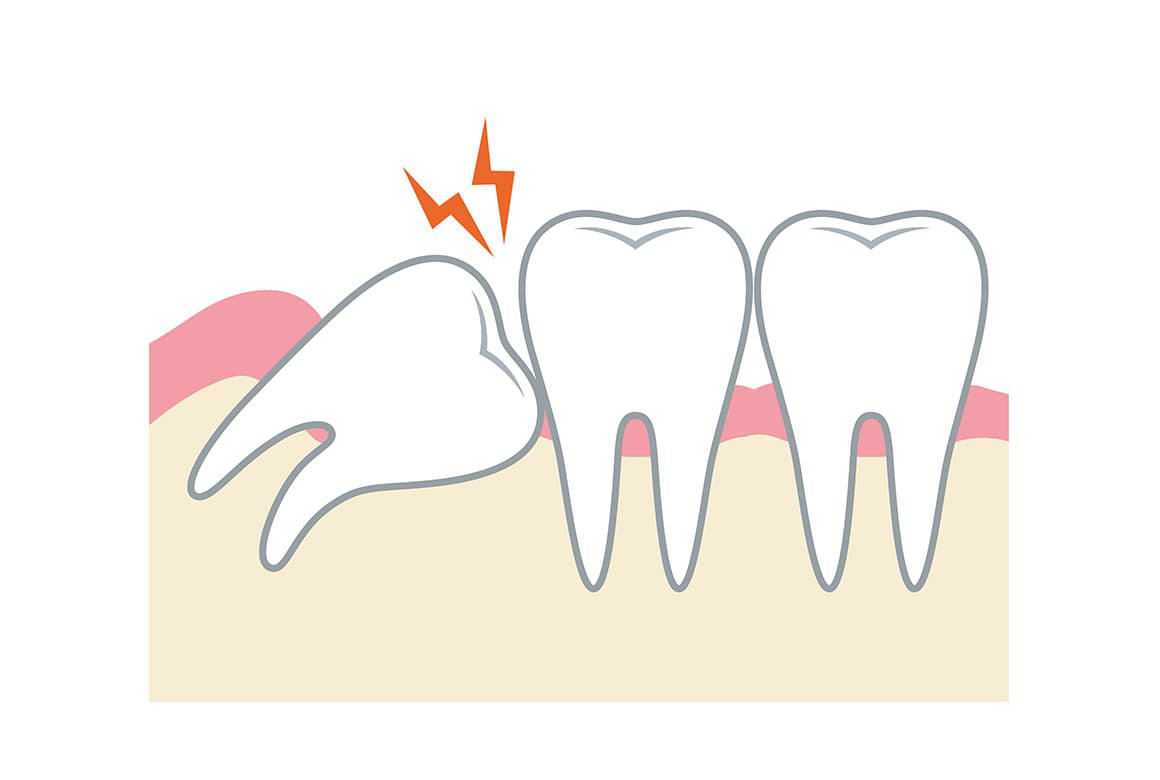

親知らずは、前歯から数えて8番目にあたる歯であり、大きな奥歯(大臼歯)の中では、前から数えて3番目に相当します。これは専門用語で、「第三大臼歯」と呼ばれる歯です。親知らずは生える場合と生えない場合がありますが、生える場合は、ほとんどのケースで10代後半から20代前半頃に生え始めます。

「親知らずの抜歯」といっても、5分で終わるものから、処置に1時間近くかかる症例までさまざまです。なお次のような場合は、放置するとトラブルが起きる可能性が高いため、抜歯をおすすめることがあります。

- きちんと生える見込みがない